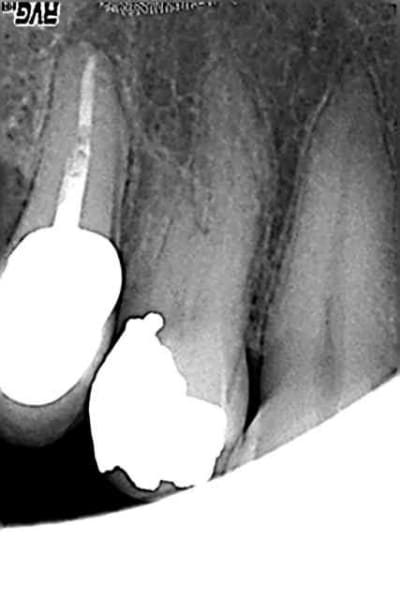

Mme Z, qui vient de loin exprès pour moi (mais dites lui ! Dites lui !) je me dis sera le cobaye idéal. Je suis sur 14, j'ouvre la piaule, je pose la digue toukomondidanleboukin, trouve le palatin, du mal à trouver le vestibulaire... Finalement je trouve. Et paf, â coté, perfo. Enfin, que je me dis... Radio. Et non. Pas perfo. un MV ! Je me suis dit que j'étais en plein dans le bouquin qui ne nous montre que des canaux supplémentaires. Là j'ai deux vestibulaires, bien courbés en plus. D'avoir vus toutes ces images de dents mutantes 1h avant ça m'a porté la poisse.

Désolé pour l'incidence du cliché, je vous rassure j'en ai pris un autre, foiré aussi, mais de l'autre coté donc j'ai pu vérifier que j'étais bon pour les longueurs, sur le plan radio.

Sympa le CR. Cependant, à la radio préop, tu aurais du le voir que tu avais 3 racines non ?

ET puis, question imagerie, tu l'utiliserais pas verticalement comme pour une incisive ton capteur sur ce coup là ?

... effectivement mais pour aller prendre sous la digue (j'ai un cadre pliant, très pratique) je préfère les angulateurs "angle droit". Question d'habitude (mauvaise ?). De toute façon dès que je peux je prends la radio droite, pour avoir tout le monde...

J'ai oublié de poster la préop, on voyait du bazar mais à mes yeux de novice c'était pas 3 racines. Maintenant, ça me paraît évident !

Effectivement sur la radiographie preoperatoire on distingue clairement l'anatomie atypique, mais c'est tellement facile une fois que c'est fait de voir.